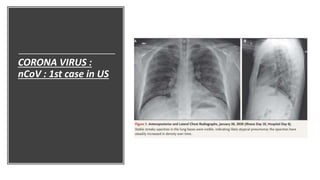

CORONA VIRUS : nCoV : 1st case in US

• December 31st 2019 -----> Clusters of cases of pneumonia in Wuhan,

Hubei Province of -------> Huanan seafood wholesale market -------> On

Jan 7th Chinese authorities confirmed these cases were associated

with novel corona virus.

• First case reported in US was in 20th January 2020.

On January 19, 35-years-old man presented to an urgent care clinic in

Snohomish County, Washington with 4 day h/o cough and subjective

fever

He disclosed he has returned to Washington on January 15 after

traveling to visit family in Wuhan.

He said he had seen the health alert systems from CDC regarding

symptoms of the disease.

Change in respiratory status was noticed starting on the evening of

hospital day 5, when the patient’s oxygen saturation values as

measured by pulse oximetry dropped to as low as 90% while he

was breathing ambient air

Given the changing clinical presentation and concern about

hospital-acquired pneumonia, treatment with vancomycin (a 1750-

mg loading dose followed by 1 g administered intravenously every

8 hours) and cefepime (administered intravenously every 8 hours)

was initiated.

Given the radiographic findings, the decision to

administer oxygen supplementation, the patient’s

ongoing fevers, the persistent positive 2019-nCoV RNA at

multiple sites, and published reports of the development

of severe pneumonia at a period consistent with the

development of radiographic pneumonia in this patient,

clinicians pursued compassionate use of an

investigational antiviral therapy